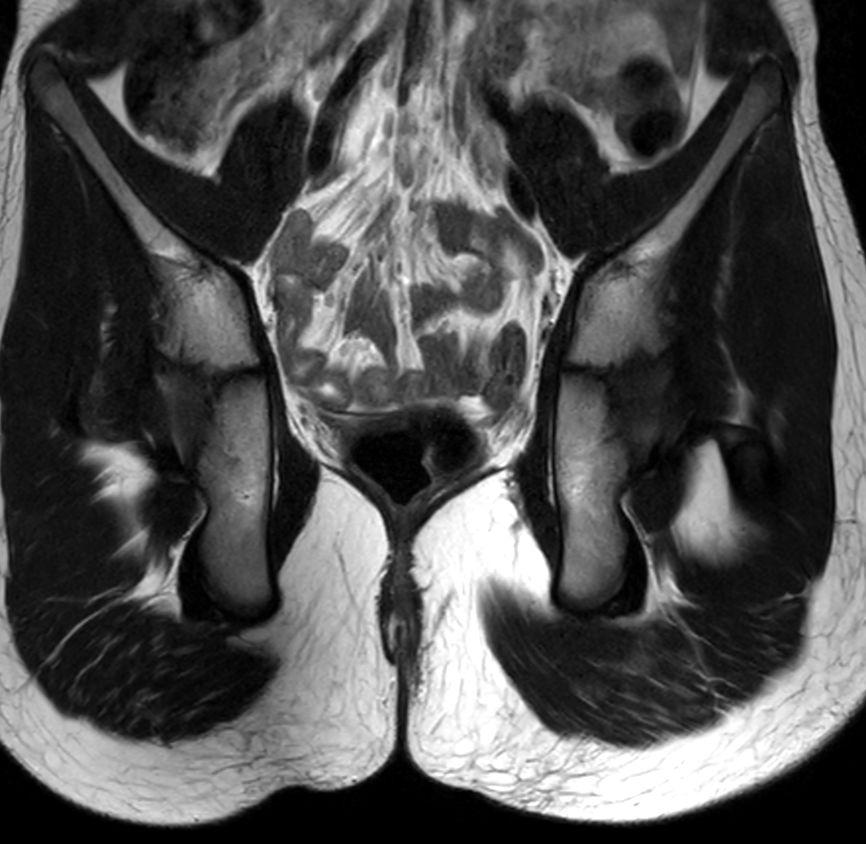

8 years old pediatric patient with a fistula in the pelvis. MultiVane XD is used to achieve high resolution diagnostic images, even in the case of severe patient motion. Integration of Compressed SENSE acceleration technique enables speeding up of the entire exam.

Coronal T2w TSE MultiVane XD